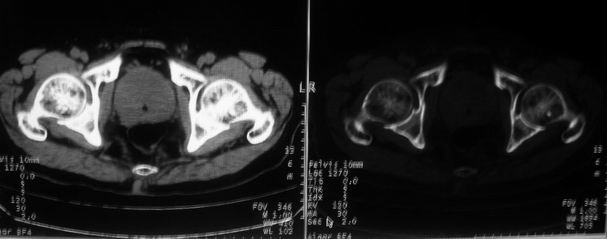

男,85岁,排尿困难。骶椎有问题吗?

前列腺明显增大,突入膀胱,各叶比例协调,密度均匀,精囊腺及精囊角正常;考虑良性增大。

1)前列腺明显增大,突入膀胱,各叶比例协调,密度均匀,精囊腺及精囊角正常;考虑前列腺增生症并阻塞性膀胱炎。2)骶椎右侧类似囊状骨质密度减低区,边缘骨质硬化,其内为软组织密度影填塞,相邻之骶椎椎管受压变形;考虑为骶椎右侧囊肿或神经纤维瘤。

建议:行mri检查。